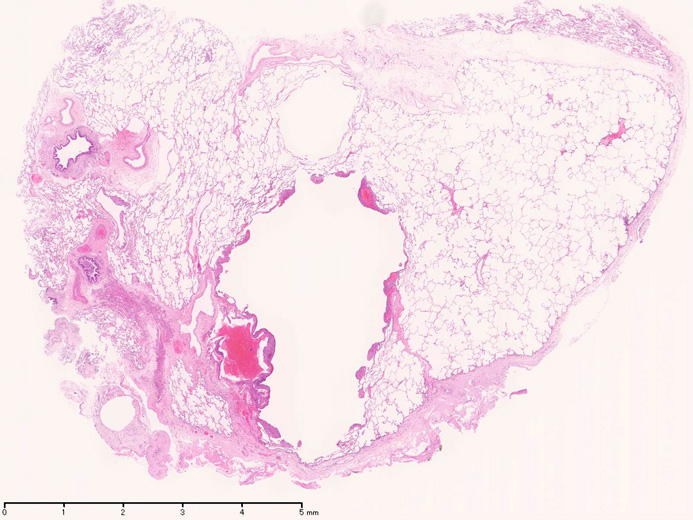

LAMの組織病理

LAMの肺病変

嚢胞周囲または肺血管, リンパ管, 細気管支にそうLAM cellの浸潤, 集簇を特徴とする。LAM cellには2種類が認められ, 小型紡錘形細胞と細胞質の豊富な類上皮様細胞があり, 紡錘型は主に集簇巣の中心に存在し増殖能が高い。 類上皮様LAM cellは辺縁部に多く, 増殖能は低いがHMB45を強く発現している。

嚢胞形成はLAM cellの増殖と関連しており, 細胞が産生するmatrix metalloproteinases(MMPs)による組織破壊によるらしい。